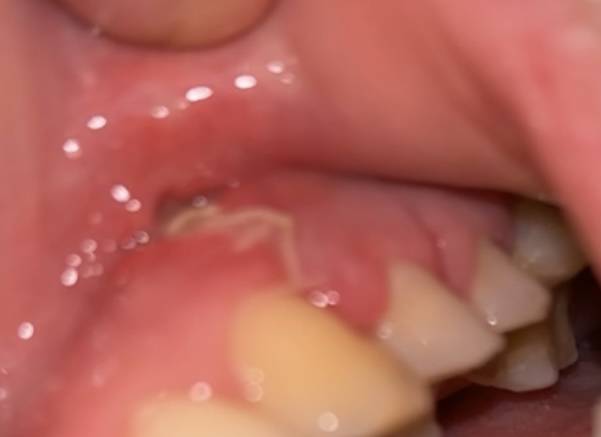

Het is dus 6 dagen geleden, en ik merk dat ik boven een hechting een gaatje heb. Vandaag heb ik een beetje erop gedrukt, en er kwam bruin/rood achtig uit. Niet loperig, niet heel dik. Ik heb af en toe ook een zoetige smaak in mijn mond. Alsof ik lichtjes de smaak van verdoving proef.

ook merk ik dikke verharding/zwelling bij de overvang van tandvlees naar wang zegmaar. het gaat vd ene hechting naar de ander. het voelt niet hetzelfde als de zwelling wat ik had door de ontsteking. Deze was rond. Wat ik nu voel, is echt een rechthoek vorm.

Bv a= hechting , - = verdikking. Dan is het zeg maar a—-a. Als je snapt wat ik bedoel. (op de foto aangeduid met groene streep)